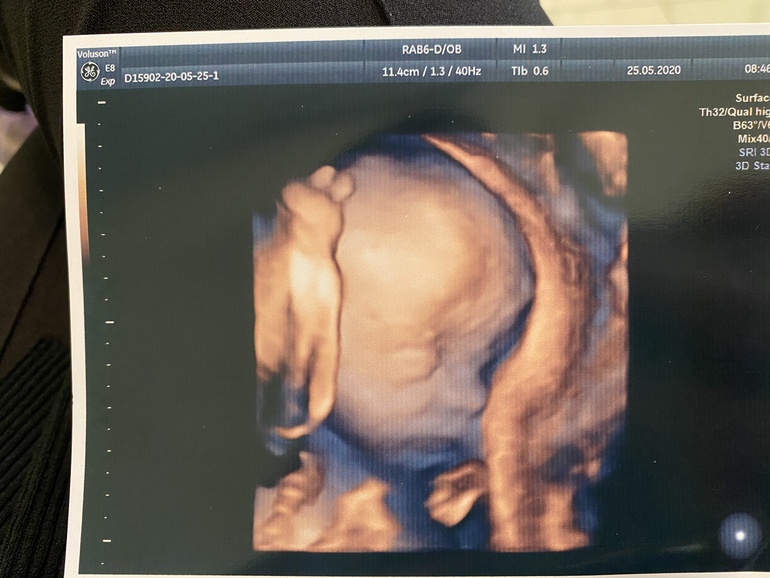

По месячным 22.2, по узи поставили ровно 22 недельки . Весим мы 526 гр, рост 28 см 🥰Девочка осталась девочкой 😌 доказательство тоже сняли 😉 все хорошо с малышкой , растём , развиваемся🙏🏻